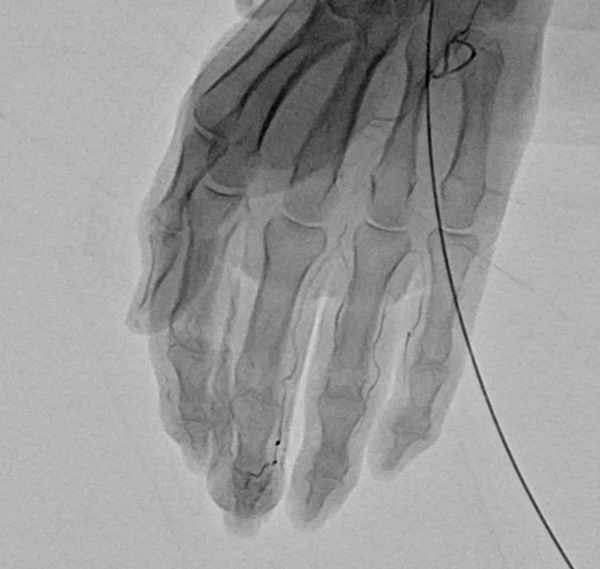

動注療法では、エコーを使用して手関節または足関節付近の動脈に細い針を刺し、溶けにくい薬液を注入します。この薬液が「モヤモヤ血管」のみを減らし、痛みを取り除くことを目的としています。処置は数分で終わり、疾患によっては高い除痛効果が認められます。当院では、動注療法の適応を判断するための検査(レントゲン、超音波、血液検査)を保険診療内で実施しております。検査の結果、動注療法が適応となった場合は、後日ご予約のうえ治療を行います。

まず、局所麻酔を刺入動脈の周囲に行い、カテーテルもしくは針を動脈内に挿入し、抗生物質でできた粒子を投与します。